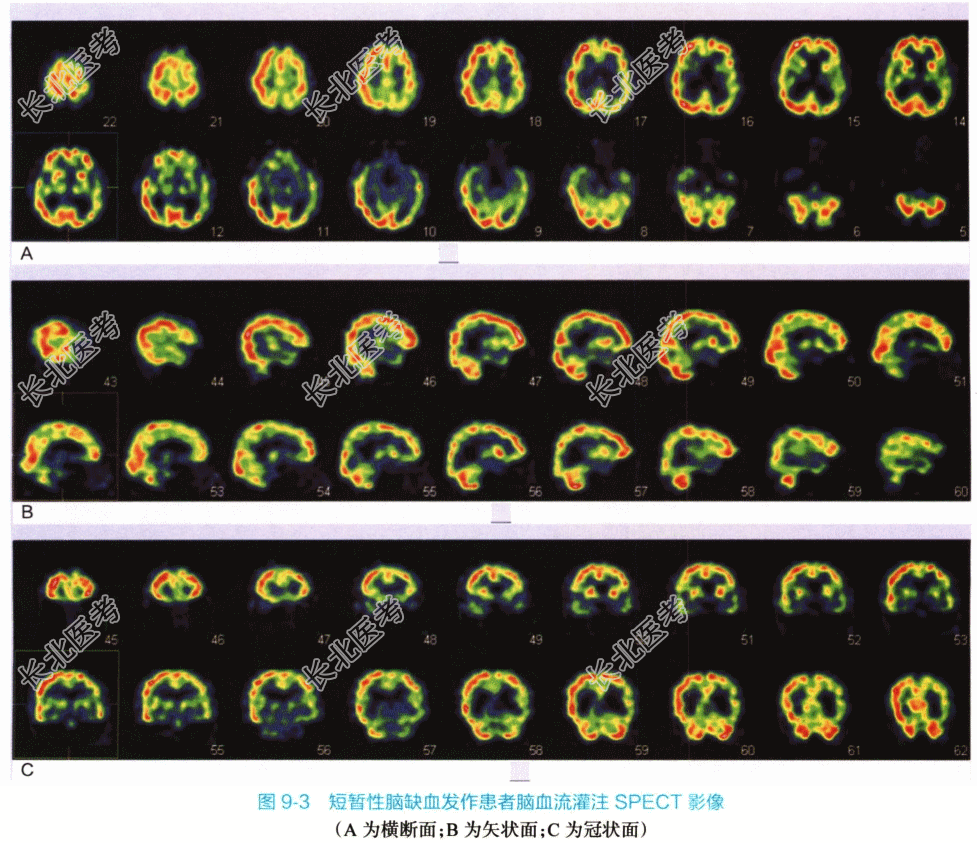

方法:视听封闭下,静脉注射⁹⁹ᵐTc-ECD740MBq,30min后行SPECT脑断层显像,图像经处理获得脑部横断、冠状和矢状三种断面图像。

检查表现:脑血流断层影像清晰,中线结构影居中,脑组织形态大致正常,脑组织局部血流显像剂分布不均匀,可见左侧顶叶、颞叶局部脑血流显像剂分布稀疏区,其余部位脑血流显像剂分布未见明显异常。